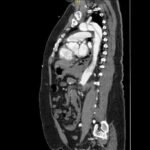

Acute aortic dissection is a life-threatening event caused by separation of the aortic layers that requires prompt management and surgical consultation. We present the case of a 53-year-old male who developed acute, severe chest pain radiating to his back at a community hospital and was transferred to a tertiary center for definitive surgical management. The patient’s aortic dissection was diagnosed via computed tomography angiography. He was started on rate-control and blood pressure medications, and was admitted emergently to the operating room. Emergency physicians should obtain immediate surgical consultation, promptly start medications for rate and blood pressure control, and administer analgesia in order to stabilize their patient and decrease the shear forces that would further propagate an aortic dissection.